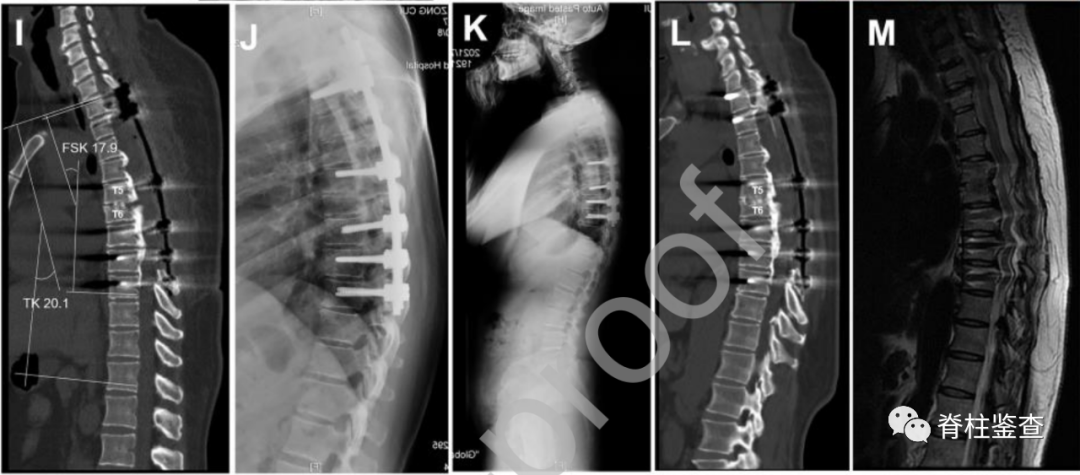

49岁女性,多节段胸椎后纵韧带骨化

(A)术前全脊柱的X线。(B) 术前全脊柱CT显示多节段后纵韧带骨化。(C) 轴位CT显示,70.6%的椎管被占据。(D) 轴位MRI显示脊髓受压和形态学改变。(E) 矢状位MRI显示胸椎管狭窄。(F) 术中显示脊髓的纵向张力(蓝色箭头)。(G) 脊柱缩短后,张力解除,脊髓变得松弛(蓝色箭头)。

(I)1个月后的矢状CT显示切除骨化的后纵韧带,缩短了脊柱,融合区的胸椎后凸角减少了16°。(J,K)12个月及45个月随访时的X线。(L) 矢状CT显示45个月时T5-6节段的融合。(M)45个月时矢状位MRI显示脊髓充分减压。